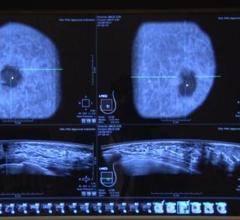

Just a few short years ago, the only options for breast imaging were 2-D mammography, but thanks to rapidly advancing ...

Dense breast tissue can mask the appearance of tumors and limit the performance of mammography. When used as an adjunct ...

Volpara now offers products to track breast density in mammography, X-ray radiation dose and analytical data. The ...